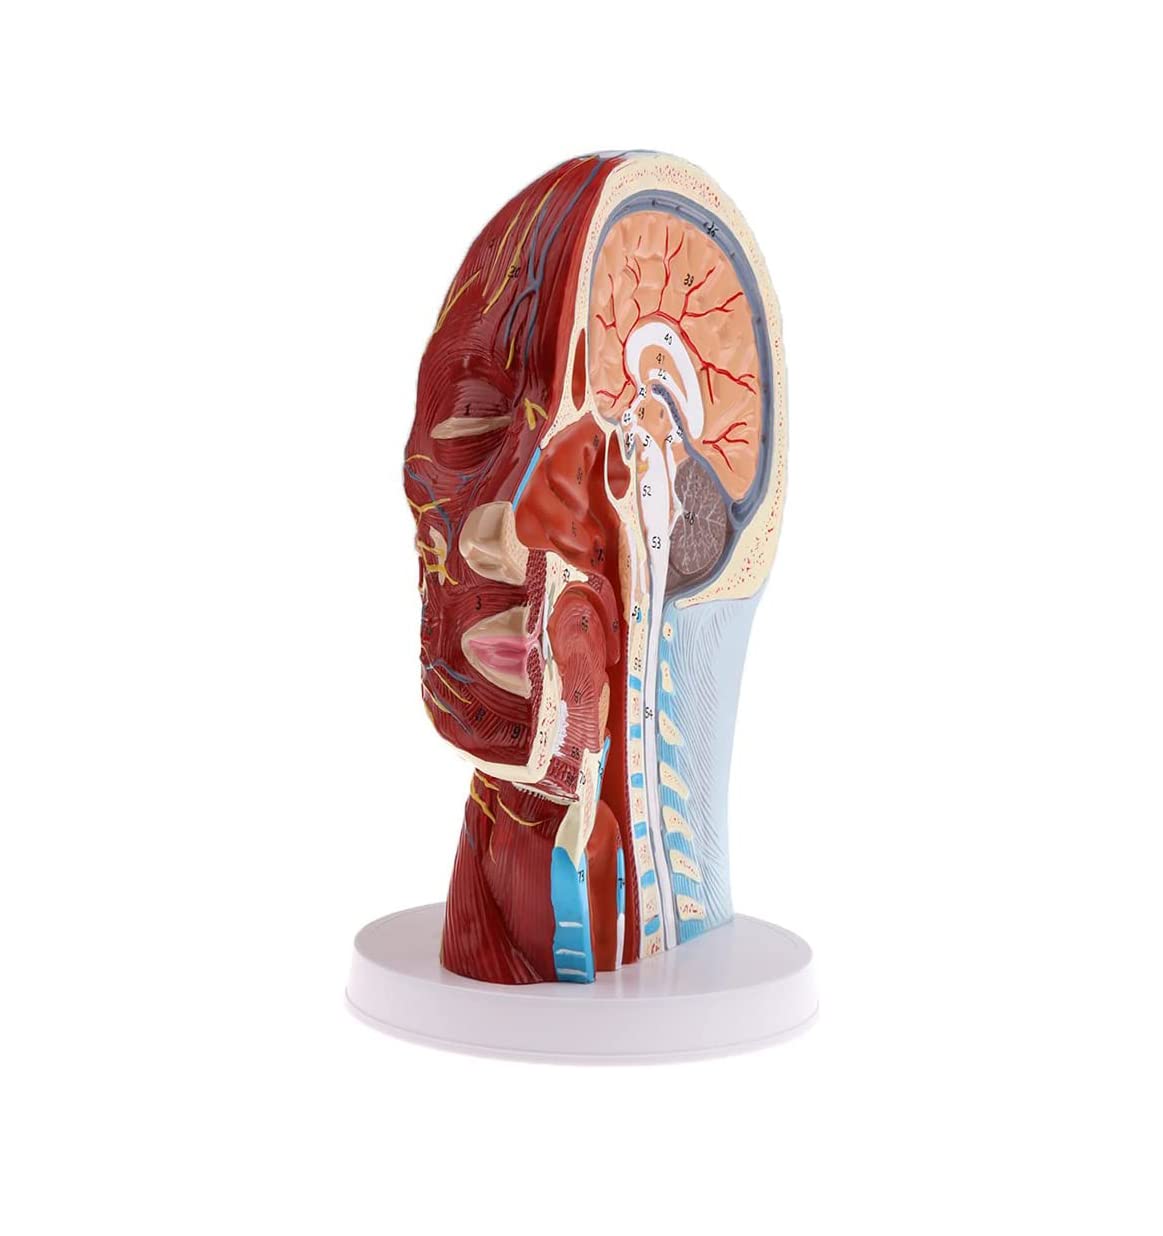

Description:A natural lifesize superficial neurovascular muscle modelMaterial: PVC, PC programmed advanced paintingHighly accurate 3D printing and spatial structureShows details of the human right head and neck and median sagittal plane, including exposed superficial muscles of face, superficial blood vessels, nerves, and parotids of face and scalp, the inner structure of the upper respiratory tract and the sagittal section of cervical spineSuitable for teaching, display, presentation and demonstration in hospital and aesthetic field.Specification:Size: 27 x 21 x 21.5 cm/ 10.6 x 8.3 x 8.5 inchPackage Includes:1 Piece brain model